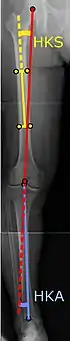

Angles commonly measured before knee replacement surgery: |

To indicate knee replacement in case of osteoarthritis, its radiographic classification and severity of symptoms both should be substantial. Such radiography should consist of weightbearing X-rays of both knees: AP, lateral, and 30 degrees of flexion. AP and lateral views may not show joint space narrowing, but the 30-degree flexion view is most sensitive for narrowing. Full-length projections also are used in order to adjust the prosthesis to provide a neutral angle for the distal lower extremity. Two angles used for this purpose are:

- Hip-knee-shaft angle (HKS),[10] an angle formed between a line through the longitudinal axis of the femoral shaft and its mechanical axis, which is a line from the center of the femoral head to the intercondylar notch of the distal femur.[12]

- Hip-knee-ankle angle (HKA),[11] which is an angle between the femoral mechanical axis and the center of the ankle joint.[12] It is normally between 1.0° and 1.5° of varus in adults.[13]